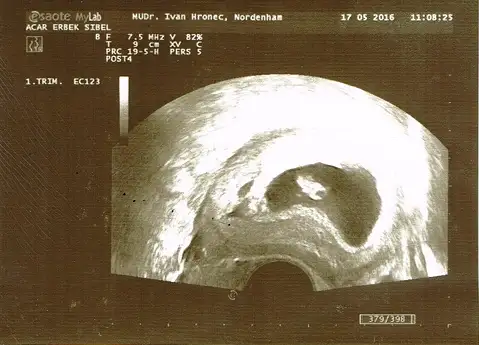

6. Hafta , 7. Hafta (ikisi de vaginal) ve 11+5 haftalık usg

yorumlarınızı heyecanla bekliyorum .